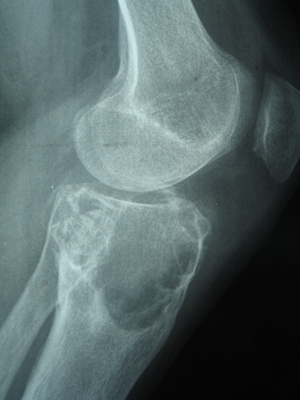

При исследовании под микроскопом фибросаркома выглядит как псевдоинкапсулированная опухоль с четкими границами. Она состоит из большого количества пучков клеток веретенообразной или круглой формы, которые разделены волокнами коллагена. Рост имеет инфильтративный и деструктивный характер.

Чтобы определить тип опухоли, необходимо провести гистологическое исследование. Обычно это становится возможным после полугода с начала образования.

Диагностика фибросаркомы обычно включает физический осмотр, медицинскую историю, а также различные визуализирующие исследования, такие как рентген, МРТ или КТ. Для подтверждения диагноза может потребоваться биопсия, при которой образец ткани опухоли исследуется под микроскопом.